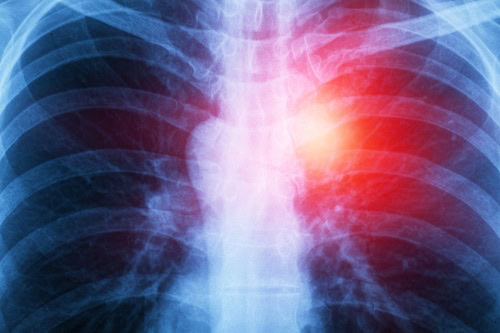

We hope that you will never be diagnosed with mesothelioma, lung cancer, or suffer a catastrophic injury, but if you are, contact us at Lipsitz, Ponterio & Comerford so we can begin the fight.